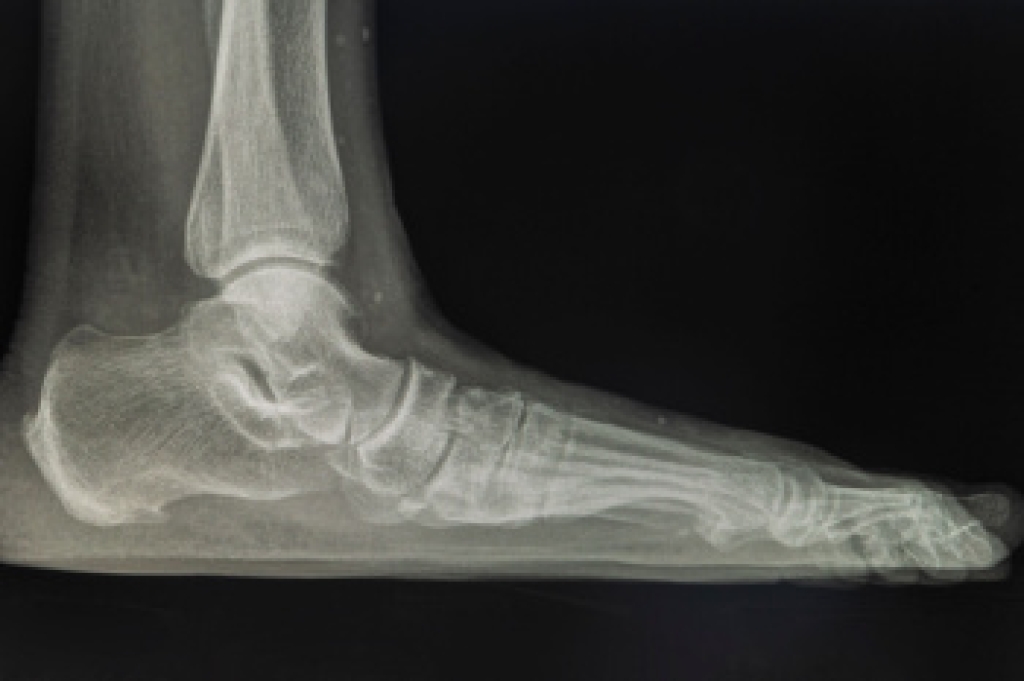

Foot orthotics are custom or prefabricated inserts designed to support and align the feet, improving comfort and function. These devices help distribute pressure evenly, reduce strain on muscles and joints, and correct abnormal foot mechanics. Orthotics are beneficial for individuals experiencing foot pain, flat feet, high arches, or conditions such as plantar fasciitis and bunions. They are also useful for athletes and individuals who spend long hours on their feet, providing additional cushioning and stability. People with diabetes may use orthotics to prevent pressure sores and ulcers. Wearing properly fitted orthotics can improve posture, reduce fatigue, and enhance overall mobility. If you have foot pain or a specific foot condition, it is suggested that you consult a podiatrist who can discuss the benefits of wearing custom orthotics.